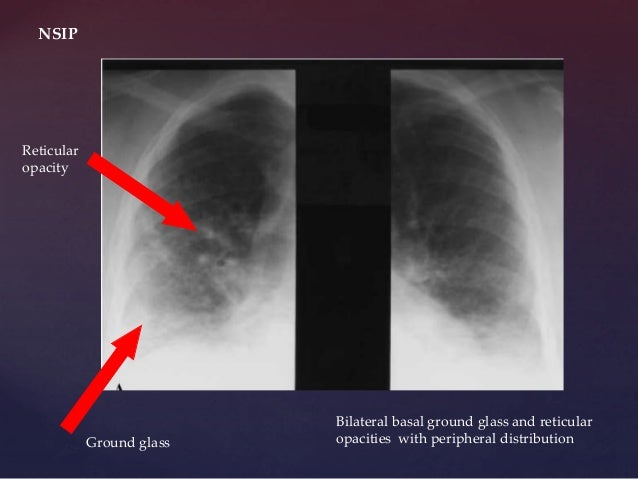

Reticular opacities seen on HRCT in patients with diffuse lung disease can indicate lung infiltration with interstitial thickening or fibrosis. Three principal patterns of reticulation may be seen. These are interlobular septal thickening, honeycombing, and irregular reticulation.

Reticulation results from thickening of the interlobular or intralobular septa and appears as several linear opacities that resemble a mesh or a net on HRCT scans. 7. The presence of reticulation is indicative of interstitial lung disease.

The reticular appearance refers to a collection of innumerable small linear opacities that together produce an appearance resembling a “net”. The pattern can be fine, medium or coarse. Fine and medium patterns are shown here. Reticular patterns represent interstitial lung disease.

What is reticular opacification?

In chest radiology, reticular and linear opacification refers to a broad subgroup of pulmonary opacification caused by a decrease in the gas to soft tissue ratio due to a pathological process centered in or around the pulmonary interstitium. This includes thickening of any of the interstitial compartments by blood, water, tumor, cells, fibrous disease or any combination thereof. The thickening of the interstitium can be reticular, reticulonodular, or linear where the predominant pattern is a result of the underlying pathological process.

The reticular interstitial pattern refers to a complex network of curvilinear opacities that usually involved the lung diffusely. They can be subdivided by their size (fine, medium or coarse). The subdivision refers to the size of the lucent spaces created by the intersection of lines:

Fine reticular opacities are reliable evidence of interstitial lung disease that requires consideration of a variety of acute and chronic diseases. Acute interstitial disease is most often the result of interstitial edema or pneumonia. Both may spread through the bronchovascular and septal interstitium. Involvement of the interlobular septa in the periphery of the lung are described as Kerley B lines. Kerley B lines are a common finding in patients with interstitial edema, but when they are more chronic they are a clue to suspect lymphangitic spread of a tumor. The collagen vascular and idiopathic interstitial lung diseases cause interstitial scarring that is more disorganized and does not spare the normal interstitial septa. Fine reticular opacities may be evidence of an early stage of these diseases.

The diffuse, fine reticular pattern (see Fig. 18.1 ) is one of the most reliable patterns for identifying diffuse interstitial disease. Because this pattern is linear, the lines must be distinguished from the normal pattern of blood vessels. In the early stages of an interstitial disease, this may be impossible by chest radiography, and high-resolution computed tomography (HRCT) may be required to confirm minimal interstitial disease. Interstitial diseases may spread throughout the bronchovascular or the septal interstitium while fibrotic diseases destroy the normal lung tissues, but both processes cause fine reticular opacities.